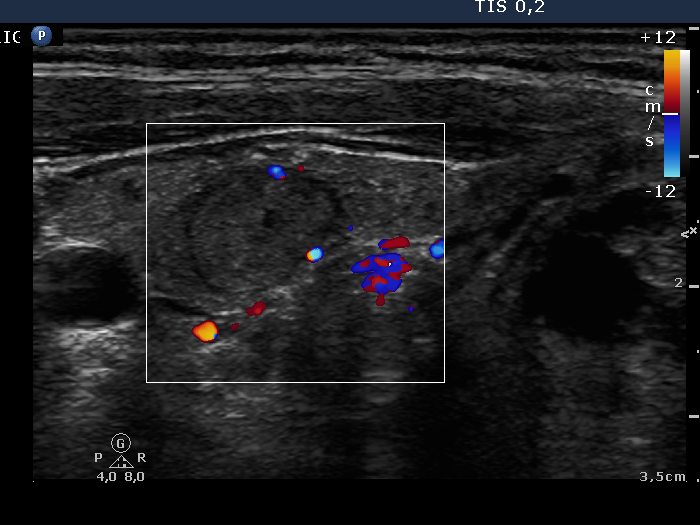

Ultrasonography: The right lobe contained an echonormal nodule, while there were multiple lesions within the left lobe. These were hyperechogenic and presented halo sign and perinodular blood flow.

Combined ultrasonographic-cytological diagnosis was benign lesion with great probability: colloid goiter with extensive oxyphilic metaplasia.